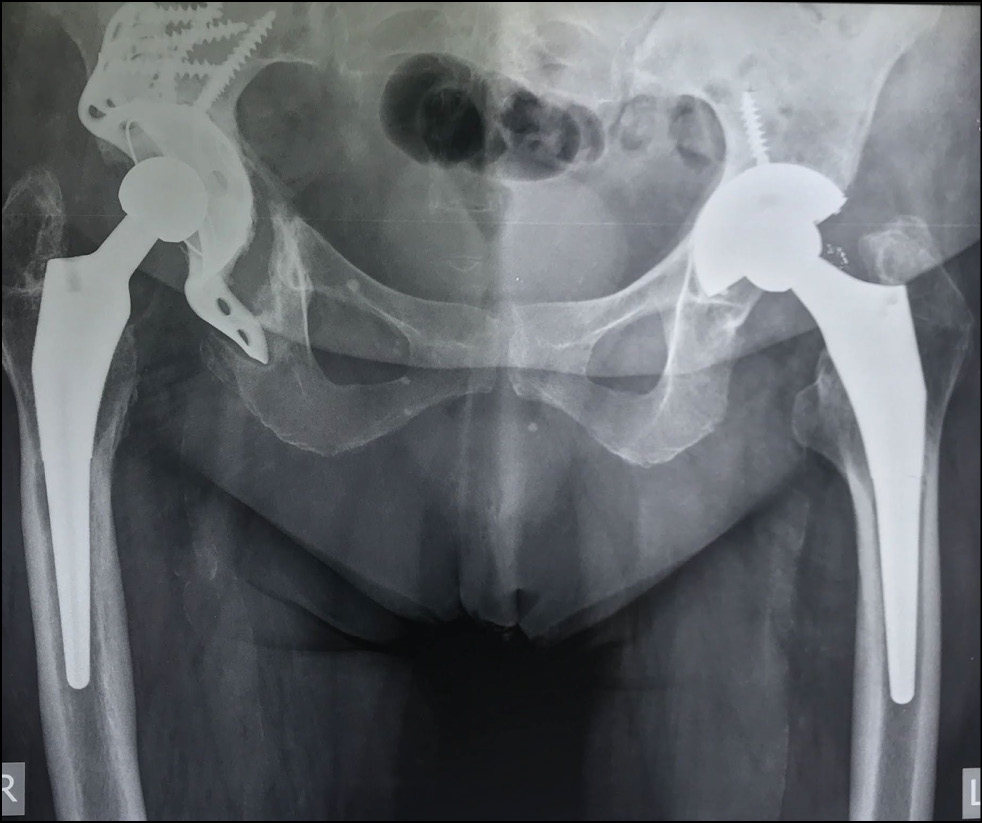

Six months after surgery, no negative dynamics on control radiographs were observed. The HHS, WOMAC, and VAS scores were 82, 15, and 30 (mm) points, respectively. Despite a slight increase in the severity of pain syndrome according to the VAS score, the patient noted improvement in the bearing capacity and functional results of the operated limb. No significant changes in the evaluation scales were noted at the subsequent follow-up examinations (1 year after surgery and once a year thereafter). At the time of writing, >4 years have elapsed since the operation. Data obtained four years after surgery did not show negative dynamics on control radiographs (Fig. 8). The pain syndrome slightly increased and corresponds to 32 (mm) points on the VAS scale. On the HHS scale, the hip joint function corresponded to 74 points, and social adaptation according to the WOMAC scale corresponded to 35 points. The patient is under dynamic observation.

Fig. 8. Postoperative control X-ray 4 years after the operation.